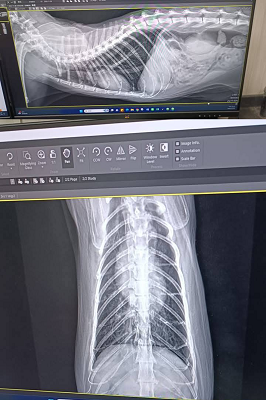

原本是先讓乖豹再留在台北安養之家觀察一小段時間,希望確定健康無虞後,再讓他回到熟悉的大湖安養之家,但在2021年1月,照護員回報乖豹食慾體重都有漸降,1月23日呼吸看來急促,立刻約診沐恩醫院檢查,檢查結果,體溫40.3度,超音波及X光檢查發現胸腔有不明團塊及胸水,給予鎮定後抽出了有膿的胸水,當天辦理住院打泰寧抗生素針,醫師研判是嚴重的細菌感染和發炎造成膿胸,住院2天時,紅血球有持續降低的情況,血容比低到21,1月25日放置胸管引流、沖洗胸腔並引流膿水,每日都需要血檢及沖洗胸腔,在狀況嚴重會需要開胸手術移除胸腔中的膿包及清創,可能會需要輸血,幸好乖豹的食慾精神都有逐漸變好、血容比也有慢慢回升,至2月4日胸管沖洗出都已是乾淨的水,食慾精神也都穩定,醫師認為已可出院自行照護醫療,因治療剃掉肚子一大片毛的乖豹,讓大家很心疼,怕他冷為他穿上可愛又保暖的衣服,也每天準備好多好吃的罐罐幫他補身體,至2月17日回診的X光檢查,原本住院時胸腔有一大一小兩個團塊已經都不見了,這樣表示大團塊只是膿包,所以吃了抗生素就消失了,3月17日再回診,血檢結果都有很好的進步,體重也有回升,膿胸的危機已經解除,只要三個月後再回診拍X光及追蹤血檢即可。

原安置於苗栗貓屋的乖豹於2025年10月與其他貓咪全數移回台北安養之家後發現體型逐漸消瘦,且背上有一顆顆肉瘤以及牙齒有鬆動的狀況,於是安排2025年11月28日於沐恩看診,醫師表示整體狀況還不錯,背上粉瘤為良性,主要是牙結石嚴重,研判體重下滑應與此有關,需盡快安排牙周手術。後再於同年12月17日進行牙周手術,後面的臼齒、2顆下門牙及上顎那一顆不好犬齒都移除,保留下面兩顆犬齒,同時背部腫塊偏良性因此暫不切除。本筆醫助是自2025年11月28日至2025年12月17日間於沐恩醫院的費用,包含看診各項檢驗、牙周手術及用藥。

2025/12/17乖豹 沐恩牙周手術

一、看診說明

手術還算順利,血壓稍微比較不容易穩定,

目前後面的臼齒、2顆下門牙及上顎那一顆不好犬齒都移除了,

下面兩個犬齒的狀況還不錯,所以還是保留下,為了縮短麻醉時間。

皮膚的腫塊看起來外觀偏良性,所以沒切除。